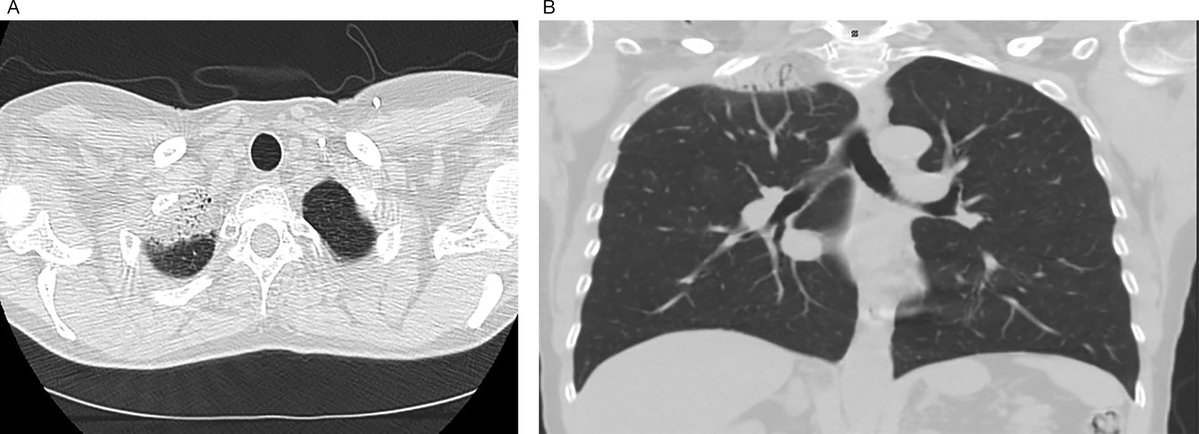

Case Report: Mediastinal Epithelioid Hemangioendothelioma in a Patient With Concurrent Early Stage Right Breast Cancer 💗🔗 ow.ly/88Kj50X8URp #BCAM25 #BreastCancerAwarenessMonth #WomensHealth #RadOncEd #MedEd